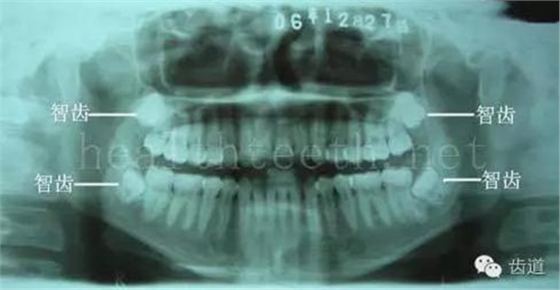

長期戴活動義齒不當或是戴不良修復(fù)義齒造成的口腔粘膜潰瘍,應(yīng)該引起高度警惕,因為這種潰瘍?nèi)菀装┳?/span> 黑毛舌 舌息肉,該患者同時伴有胃、食管息肉,后來看內(nèi)科了,具體情況不詳 四、孩子的牙齒問題 乳牙未退,牙根穿出牙齦對上唇粘膜造成刺激 乳牙滯留,也是孩子在退牙過程中最容易遇到的問題 五、牙齒發(fā)育上的問題 變色牙 氟斑牙 釉質(zhì)發(fā)育不全 四環(huán)素牙 牙神經(jīng)治療后的牙齒變色 10歲孩子剛剛萌出的牙齒變色 2、埋伏牙 左上乳3滯留,恒3未見萌出,曲面斷層片顯示牙齒埋伏 通過CT片確定埋伏牙齒具體的位置,顯示距離左側(cè)上頜竇很近,偏唇側(cè),這為手術(shù)定位提供了方便 手術(shù)中切斷、完整拔出,未損傷上頜竇 其他埋伏牙 3、多生牙 病例1 病例2 病例3,同時多生兩顆牙齒 4、各種畸形牙 畸形過小牙 融合牙:恒牙和乳牙都可以發(fā)生融合的情況(兩顆牙齒長在了一起) 畸形中央尖:在牙齒的中央,兩個牙尖之間又多長出一個牙尖,由于進食的磨耗很容易造成磨穿,神經(jīng)就會與外界相通,出現(xiàn)牙髓炎的癥狀 六、牙齒的外傷 牙冠折斷 牙根折斷 烤瓷牙打樁修復(fù)后牙根折斷 外傷后牙齒的全脫位,應(yīng)該保留牙齒盡早做再植手術(shù) 七、牙齒的慢性損傷 牙頸部楔狀缺損 牙冠劈裂及完整拔除后的情況 牙根縱裂及拔除后的情況 牙隱裂,牙齒表面有肉眼看不到的裂紋,細菌通過其進入牙髓,容易出現(xiàn)牙髓炎癥狀,嚴重可以造成牙齒的劈裂 這是一位來中國學(xué)習(xí)的俄羅斯大學(xué)生的牙齒,已經(jīng)做過了根管治療,牙齒咬合面有隱裂,通過鋼絲結(jié)扎固定,做鑄造金屬冠修復(fù)。 八、牙髓炎、根尖周炎 下面圖片都是慢性根尖周炎的病例,有了齲齒,進一步發(fā)展就是牙髓炎,如果此時沒有得到及時的治療,疾病會逐漸發(fā)展破壞到根尖的骨質(zhì),將骨質(zhì)破壞后就在牙齦上出現(xiàn)一個膿瘺,此時患者不再感覺到牙齒的疼痛了,往往忽視了治療,但是這種不痛并不是疾病好轉(zhuǎn)了,而是因為疾病的炎性滲出得到了引流,這個膿瘺會出現(xiàn)有時候變大了,有時候又變小了,但是如果不治療是不會自己愈合的,只有經(jīng)過完善的根管治療后才有好轉(zhuǎn)的可能,但是在疾病的治療中時間是起決定作用的,時間拖得越晚,好轉(zhuǎn)的可能性越小,經(jīng)過根管治療后如果膿瘺還是沒有消失,就需要做根尖刮治術(shù),如果仍然沒有好轉(zhuǎn),就只能做根尖切除術(shù)了,這對牙齒的穩(wěn)固是不利的。下面圖片中在膿瘺中插入了一個牙膠尖,是我們做根管充填用的材料,是非常軟的,就是在口腔牙齦瘺管的地方插進去,通過拍牙片可以清晰地看到它到達的位置,從而確定發(fā)病的牙齒,此處是為了讓大家看得更清楚。 門牙兩個膿瘺 烤瓷牙修復(fù)后牙齦出現(xiàn)兩個膿瘺,插入牙膠尖,牙片顯示牙膠尖到達的位置就是根尖炎癥的位置,根尖骨質(zhì)密度降低(發(fā)黑的地方) 牙齒根尖膿瘺,治療前、中、后的圖片對照,完善根管治療后膿瘺明顯消失了 牙髓炎和根尖炎治療的關(guān)鍵就是根管治療 合格的根管充填治療 不良的根管充填治療 九、關(guān)于智齒(第八顆牙) 四顆長不出來的智齒 智齒反復(fù)發(fā)炎造成的頰瘺,膿腫切開引流后面部會留疤 智齒造成的頜骨囊腫,手術(shù)切除后需要植骨 十、各種錯合畸形 開合 深覆合 深覆蓋,上頜前突 反合(地包天) 牙齒排列擁擠 來源:牙醫(yī)愛看的 KQ88口腔醫(yī)學(xué)網(wǎng)